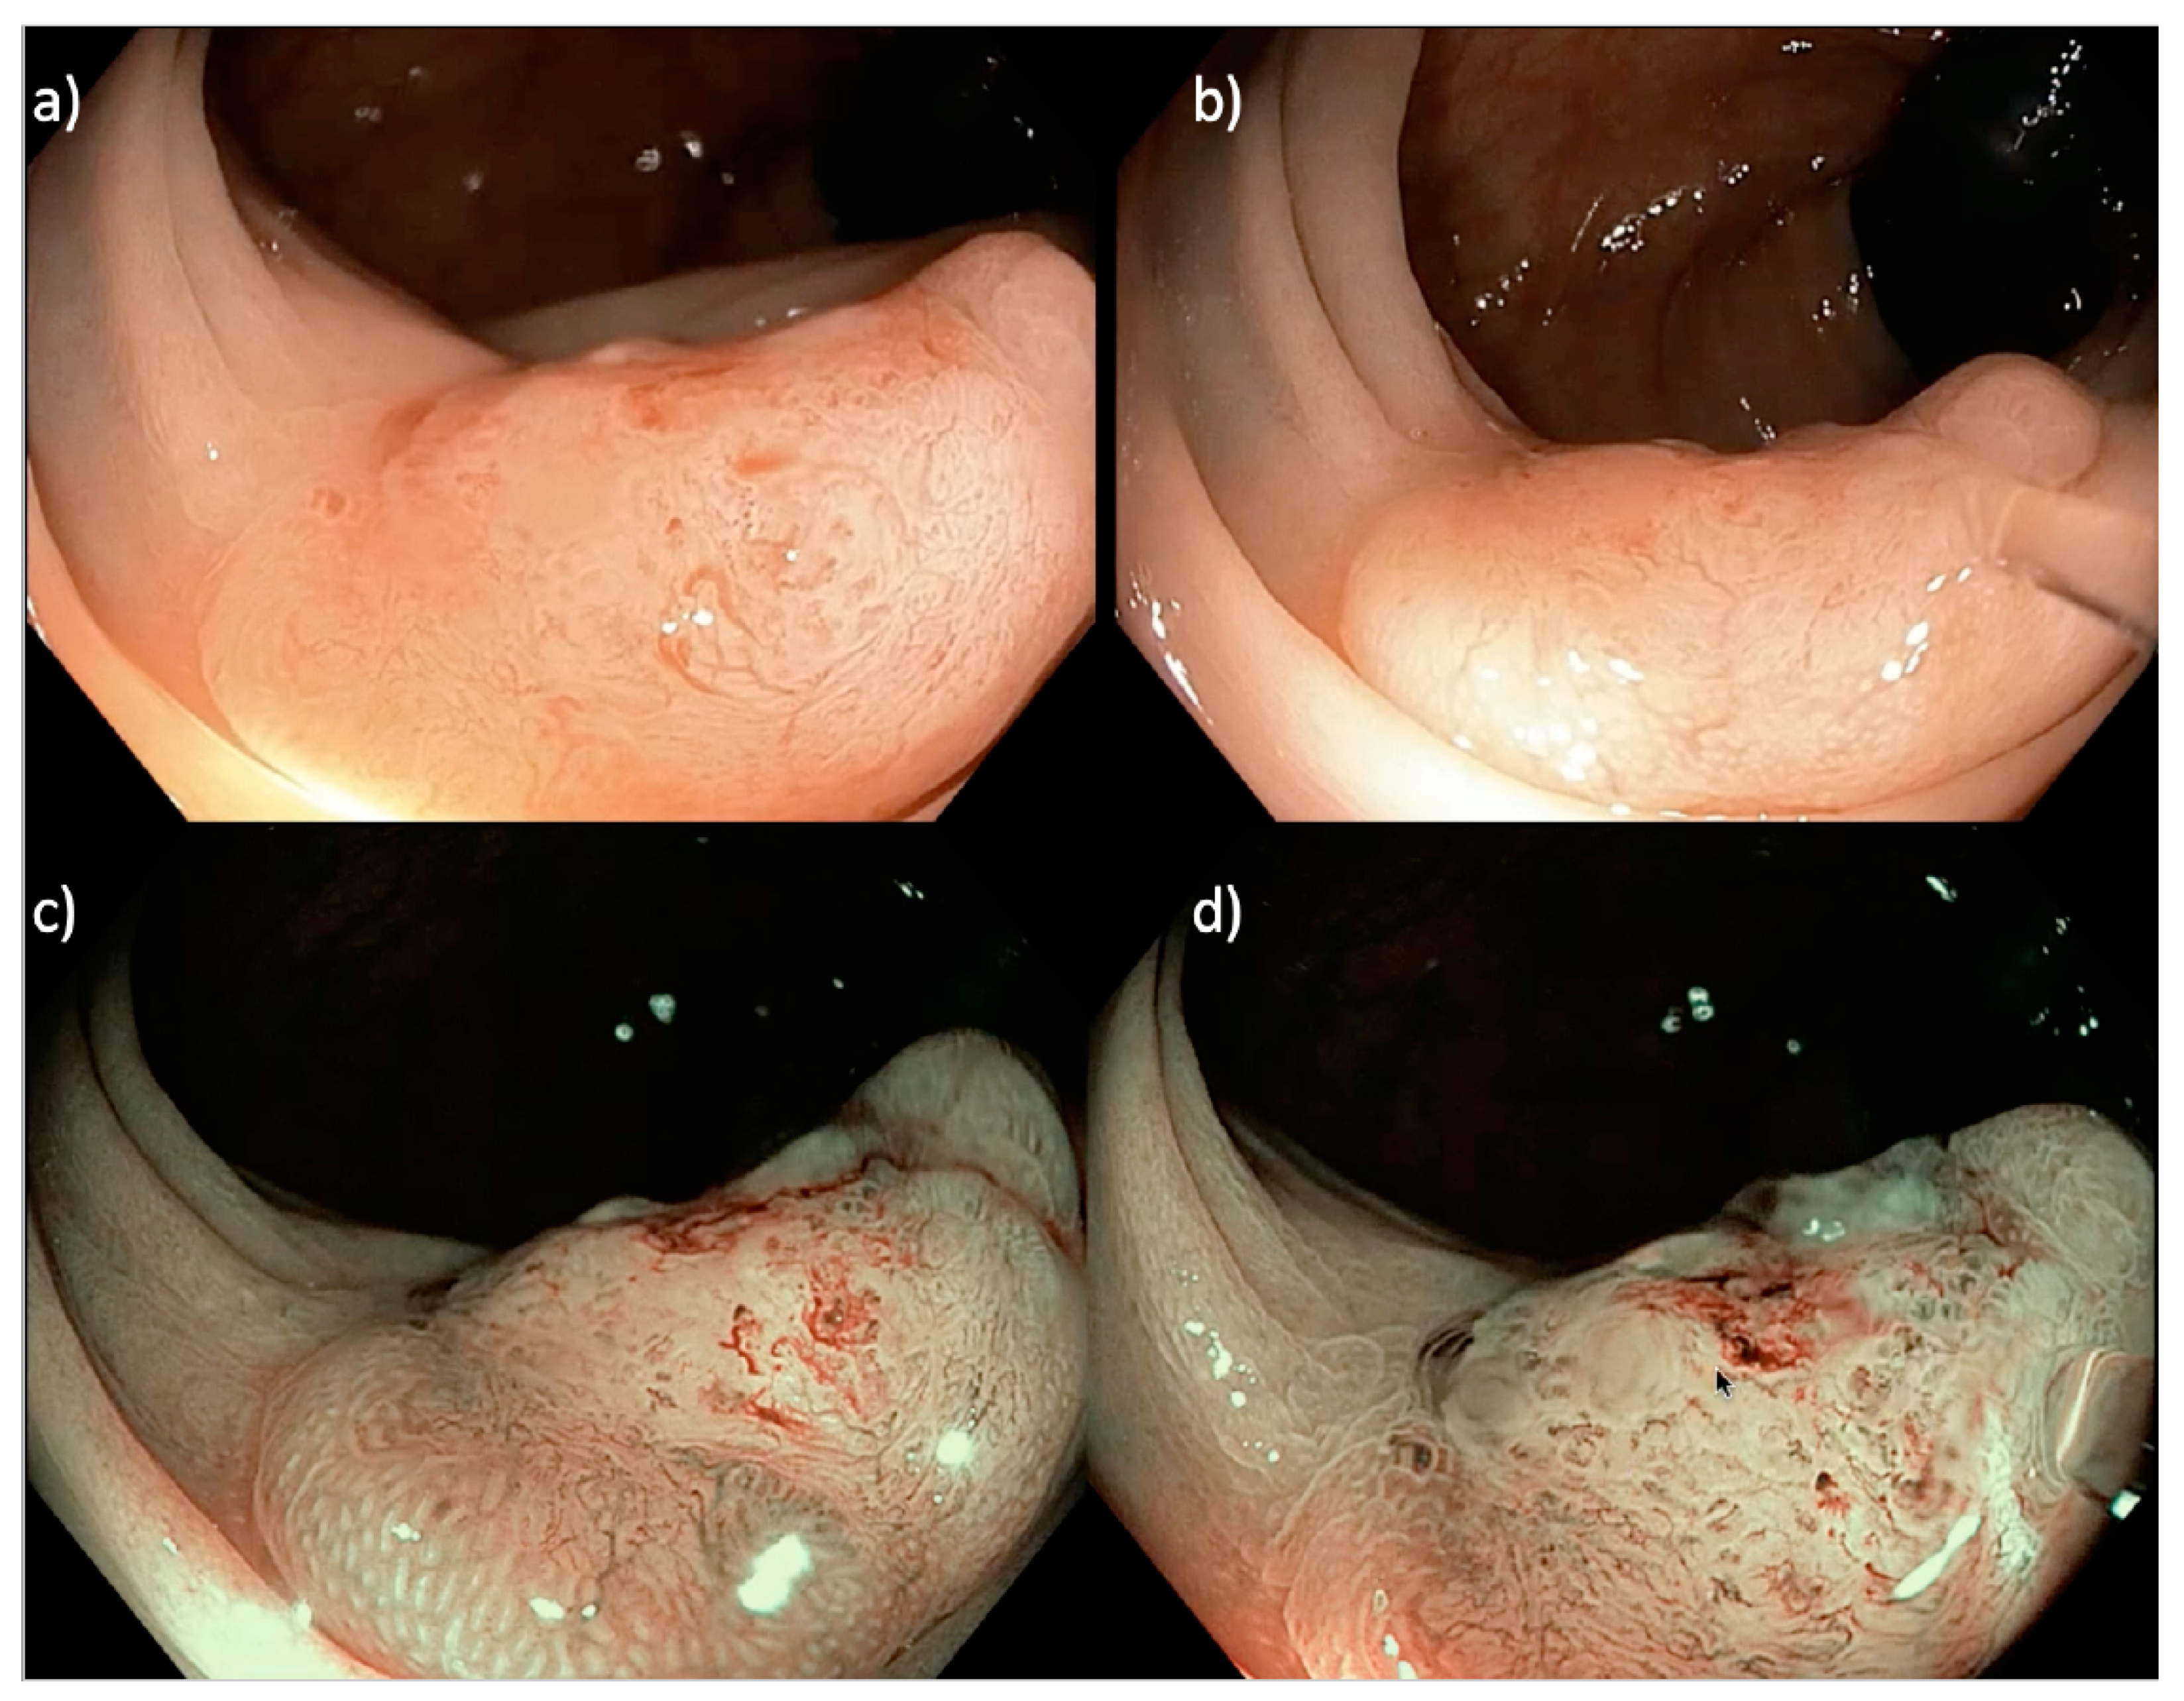

3.3. Large (>20 mm) Non-Pedunculated Colorectal Polyps